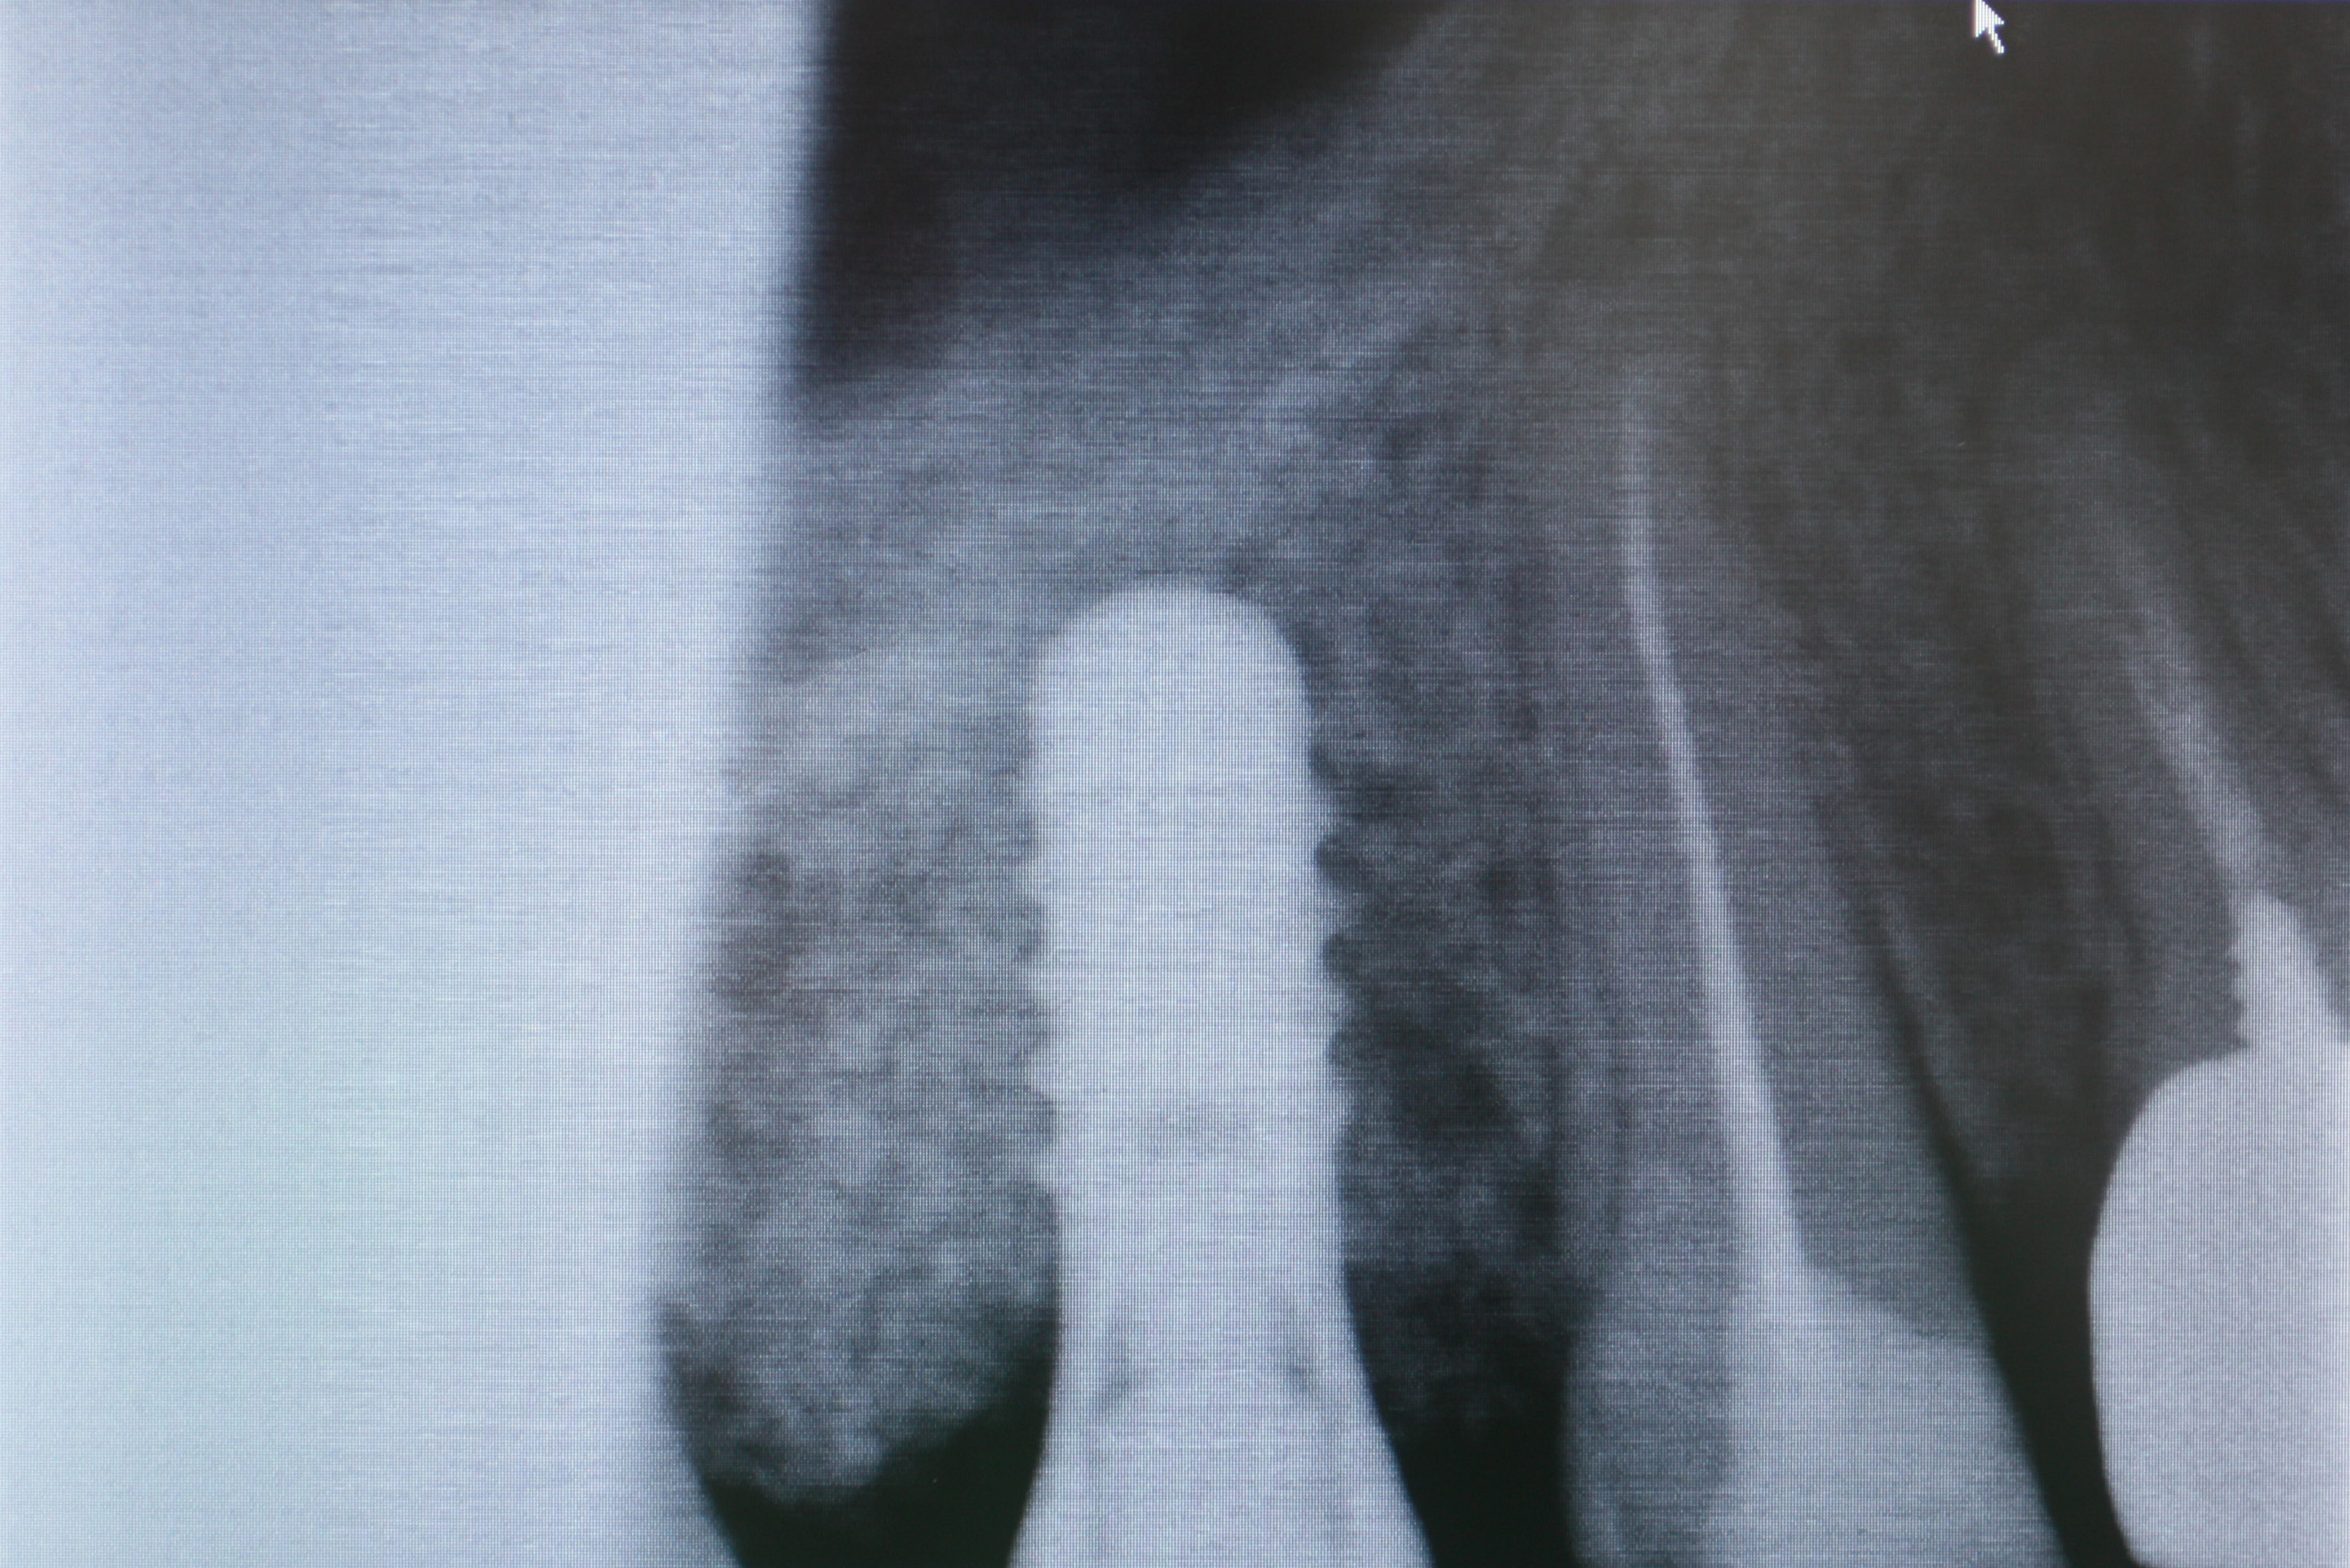

A distanza di 12 mesi viene inserito un impianto Tissue Level Straumann in sede molare superiore, con tecnica Flapless Modificata.

La paziente rimane soddisfatta del minimo disaggio post-operatorio.